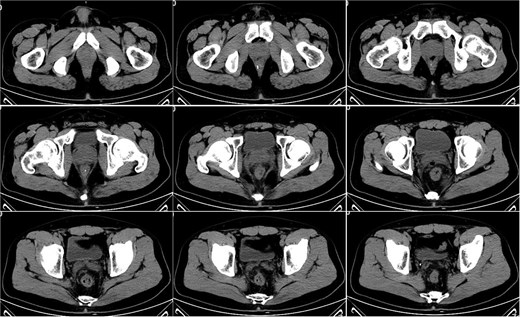

On postoperative Day 21, a follow-up pelvic CT scan indicated local gas accumulation around the rectum, suggesting an absorption phase of the infection (Fig. 4). By postoperative Day 28, a pelvic CT scan demonstrated minor gas accumulation at the anterior edge of the rectosigmoid junction, consistent with infection resolution and gas absorption in the surrounding area (Fig. 5). By postoperative Day 49, a pelvic CT scan revealed no abnormal density shadows in the perianal skin and soft tissues, with preserved fat planes (Fig. 6), indicating complete resolution of the perirectal infection and restoration of normal clinical status.